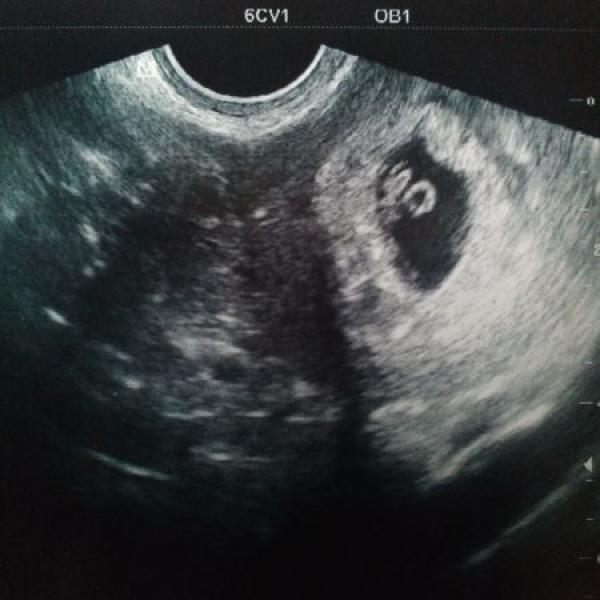

Leenkka 28.10.2015 Detail Moje malinkatý zlatíčko :€O: :h: Komentáře jsou momentálně nedostupné. Děkujeme za pochopení. Leenkka 27.10.2015 Detail Pocit obrovského štěstí :h: Komentáře jsou momentálně nedostupné. Děkujeme za pochopení.